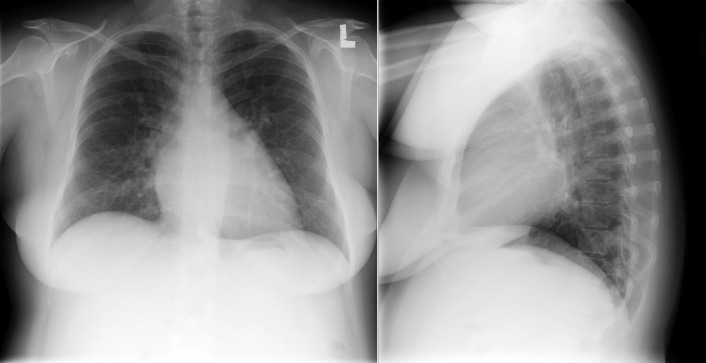

The radiographic findings of mitral stenosis ( Graphic 15-1 ; Figs. 15-1 to 15-16 ) reflect the pressure overload of the left atrium and pulmonary veins, and later of the right heart. As well, the commonly associated chronic atrial fibrillation contributes to (bi)atrial dilation. Associated rheumatic valvular lesions such as mitral regurgitation, tricuspid regurgitation, aortic insufficiency, and aortic stenosis/aortic insufficiency are common, and they alter the appearance of the heart.